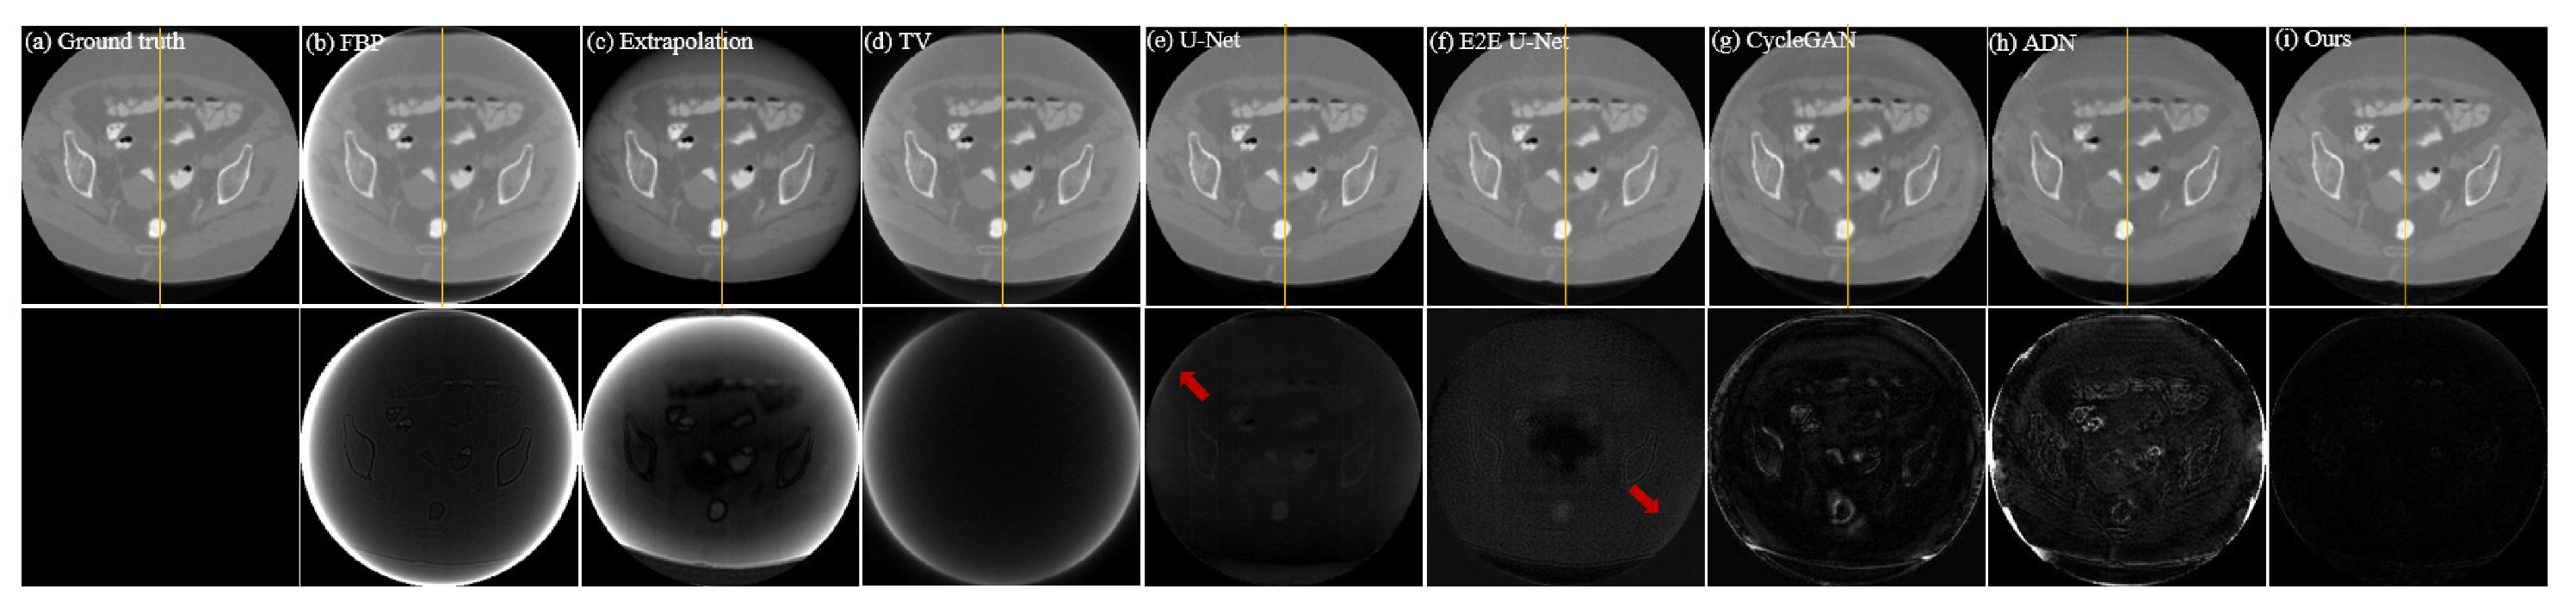

Figure 4.

Qualitative comparison of different methods on dataset CL1; (a–i) represent the ground truth and the resulting images from FBP, Extrapolation, TV, U-Net, E2E U-Net, Cycle-GAN, ADN, and our PIDNET, respectively. The second row shows the residual images derived from comparing the resulting images with ground truth. The yellow lines indicate the positions of the profile plots shown in Figure 5.

To simulate unsupervised scenarios, we only designed unpaired data in dataset CL2. Therefore, it was impossible to train supervised models on this dataset and the supervised models tested on dataset CL2 were directly transferred from dataset CL1. As both datasets CL1 and CL2 consist of clinical CT images, their similarity is relatively high. Testing the pre-trained models on dataset CL2 can be used to intuitively demonstrate the performance variation of supervised models when they are transferred between similar datasets. Table 2 displays the performance metrics of all comparative methods on dataset CL2. It is evident that the supervised models, being directly transferred from dataset CL1, exhibit a significant decline in all performance metrics. However, the final outcomes still surpass the traditional Extrapolation and TV methods, indicating the practical value of directly transferring pre-trained models. Table 2 also clearly shows that the performance metrics of our proposed unsupervised model are superior to the supervised models. This is because our model is unsupervised and can be trained without paired data. The results and residual images shown in Figure 6 support the same conclusion as Table 2. The supervised models outperform the traditional Extrapolation and TV methods, but their residuals are larger than those obtained on dataset CL1, indicating that more truncation artifacts (highlighted by red arrows) are not removed. Additionally, the comparison results of the profile plots in Figure 7 clearly demonstrate the superiority of the supervised models over traditional methods, while the profile plot from our unsupervised model is closer to the ground-truth profile plot than all comparison methods.

Figure 6.

Qualitative comparison of different methods on dataset CL2; (a–i) represent the ground truth and the resulting images from FBP, Extrapolation, TV, U-Net, E2E U-Net, Cycle-GAN, ADN, and our PIDNET, respectively. The second row shows the residual images derived from comparing the resulting images with ground truth. The yellow lines indicate the positions of the profile plots shown in Figure 7.